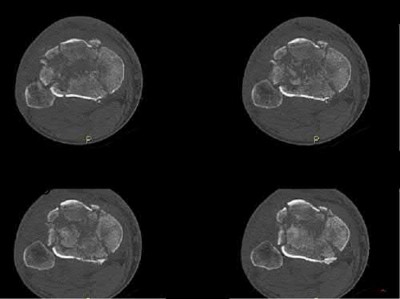

Question 19

A 28-year-old male sustains a closed comminuted tibial shaft fracture.

Two hours post-injury, he develops severe leg pain unyielding to narcotics. His blood pressure is 120/80 mmHg. Intracompartmental pressure monitoring is performed. Based on current guidelines, which measurement dictates an emergent 4-compartment fasciotomy?

Explanation

Acute compartment syndrome is classically defined by tissue hypoperfusion. The absolute compartment pressure is less reliable than the differential pressure (Delta P). A Delta P (Diastolic Blood Pressure minus Compartment Pressure) of less than 30 mmHg is an absolute indication for emergency fasciotomy, as capillary perfusion gradient is lost when tissue pressure approaches the diastolic pressure.